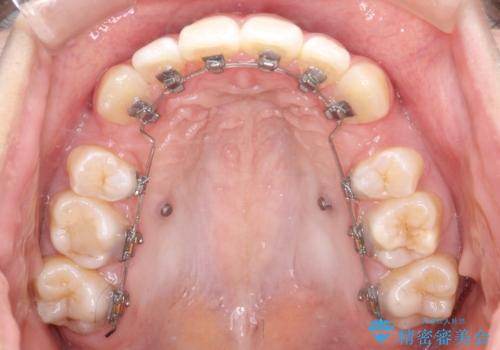

- ハーフリンガル

当院では裏側矯正という方法も提供しています。裏側矯正は、装置を歯の裏側に取り付けるため、外側からは目立ちにくくなります。この治療法は、見た目に気を使いたい方に特におすすめです。

ワイヤー矯正治療は、歯並びの問題を改善し、美しい笑顔を取り戻すための効果的な方法です。当院では経験豊富なスタッフが、患者様一人ひとりのニーズに合わせた最適な治療を提供しています。治療の詳細やご予約については、お気軽にお問い合わせください。